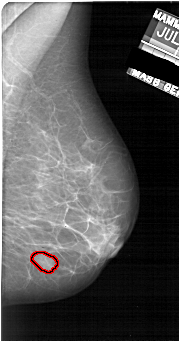

A_1922_1.LEFT_CC

LEFT_CC LINES 5311 PIXELS_PER_LINE 2536 BITS_PER_PIXEL 12 RESOLUTION 43.5 NON_OVERLAY

FILE: A_1922_1.RIGHT_CC.OVERLAY

TOTAL_ABNORMALITIES 1

ABNORMALITY 1

LESION_TYPE MASS SHAPE OVAL MARGINS OBSCURED

ASSESSMENT 3

SUBTLETY 4

PATHOLOGY BENIGN

TOTAL_OUTLINES 1

BOUNDARY